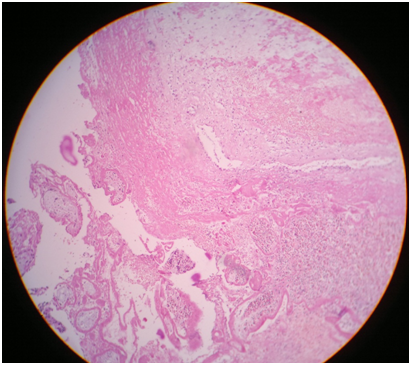

Intra operative and immediate postoperative patient received 2 units of blood transfusion. Her postoperative period was uneventful and was discharged 3 day after operation. On histopathological examination, villous structures embedded in the ovarian tissue were seen, which was confirmatory of primary ovarian pregnancy (Figure 4).

Figure 4 Histopathological examination revealed villous structures embedded in the ovarian tissue suggestive of pregnancy implanted in ovary.